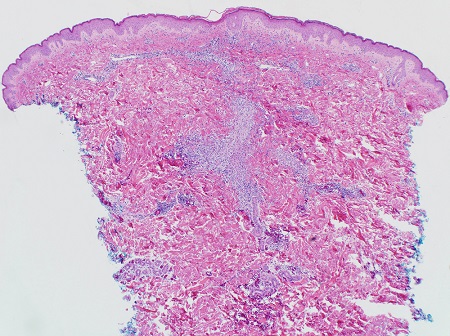

Haematoxylin- and eosin-stained sections from a lesion of miliaria crystallina demonstrates a sub-corneal vesicle situated over an acrosyringeal duct with no associated inflammatory infiltrate.

Haematoxylin- and eosin-stained sections from a lesion of miliaria profunda demonstrates an intra-epidermal spongiotic vesicle associated with an acrosyringeal duct with lymphocytic exocytosis, and a superficial perivascular infiltrate of lymphocytes and neutrophils that is denser than that seen in miliaria rubra.[Figure caption and citation for the preceding image starts]: Photomicrograph of miliaria crystallina showing non-inflammatory sub-corneal blister (H&Ex100)From Brian L. Swick's collection, used with permission [Citation ends].

[Figure caption and citation for the preceding image starts]: Photomicrograph of miliaria rubra showing intra-epidermal acrosyringeal spongiosis and underlying chronic inflammation (H&Ex400)From Brian L. Swick's collection, used with permission [Citation ends].